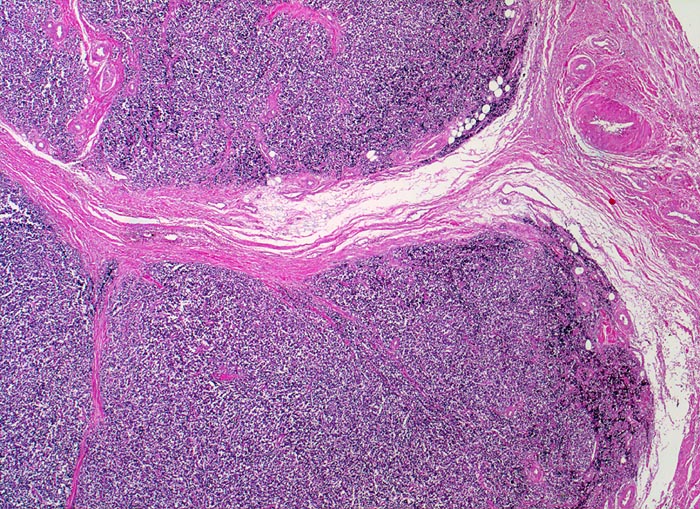

Ewing-Sarkom

Weichteile Bein

Auffallend monotoner dichter Tumorzellrasen mit lobulärer Architektur (d.h. durch Bindegewebssepten abgegrenzte Knoten).

Femuramputat mit festem grauweissem intraossärem feucht-glänzendem Tumorgewebe. Die extraossäre Weichteilkomponente ist weicher und brüchiger. Der Gewebsschnitt stammt aus der extraossären Weichteilkomponente.

Histologie

25